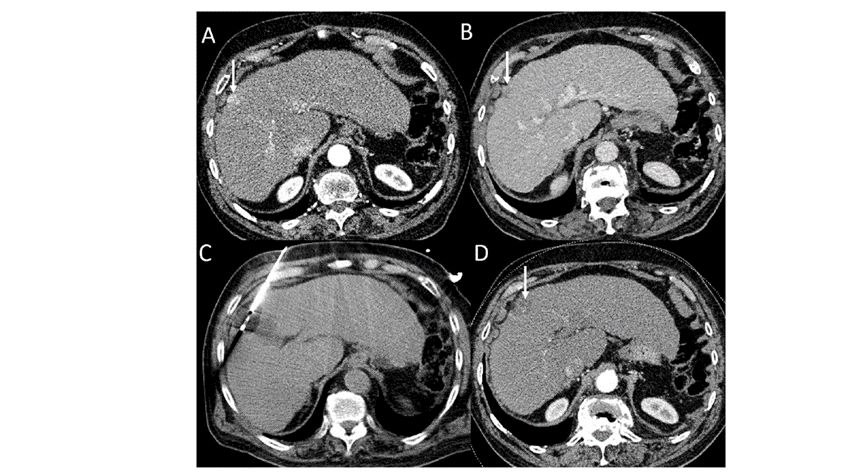

冷凍消融肝包膜下肝細(xì)胞癌

(A)動(dòng)脈期CT圖像顯示有一個(gè)包膜下結(jié)節(jié)(箭頭)。

(B)門靜脈期CT圖像顯示病灶區(qū)(箭頭)。

(C) 在手術(shù)過程中的CT顯示一個(gè)冷凍探針位于病灶內(nèi)。

(D)消融后,術(shù)后1個(gè)月影像CT顯示完全消融。